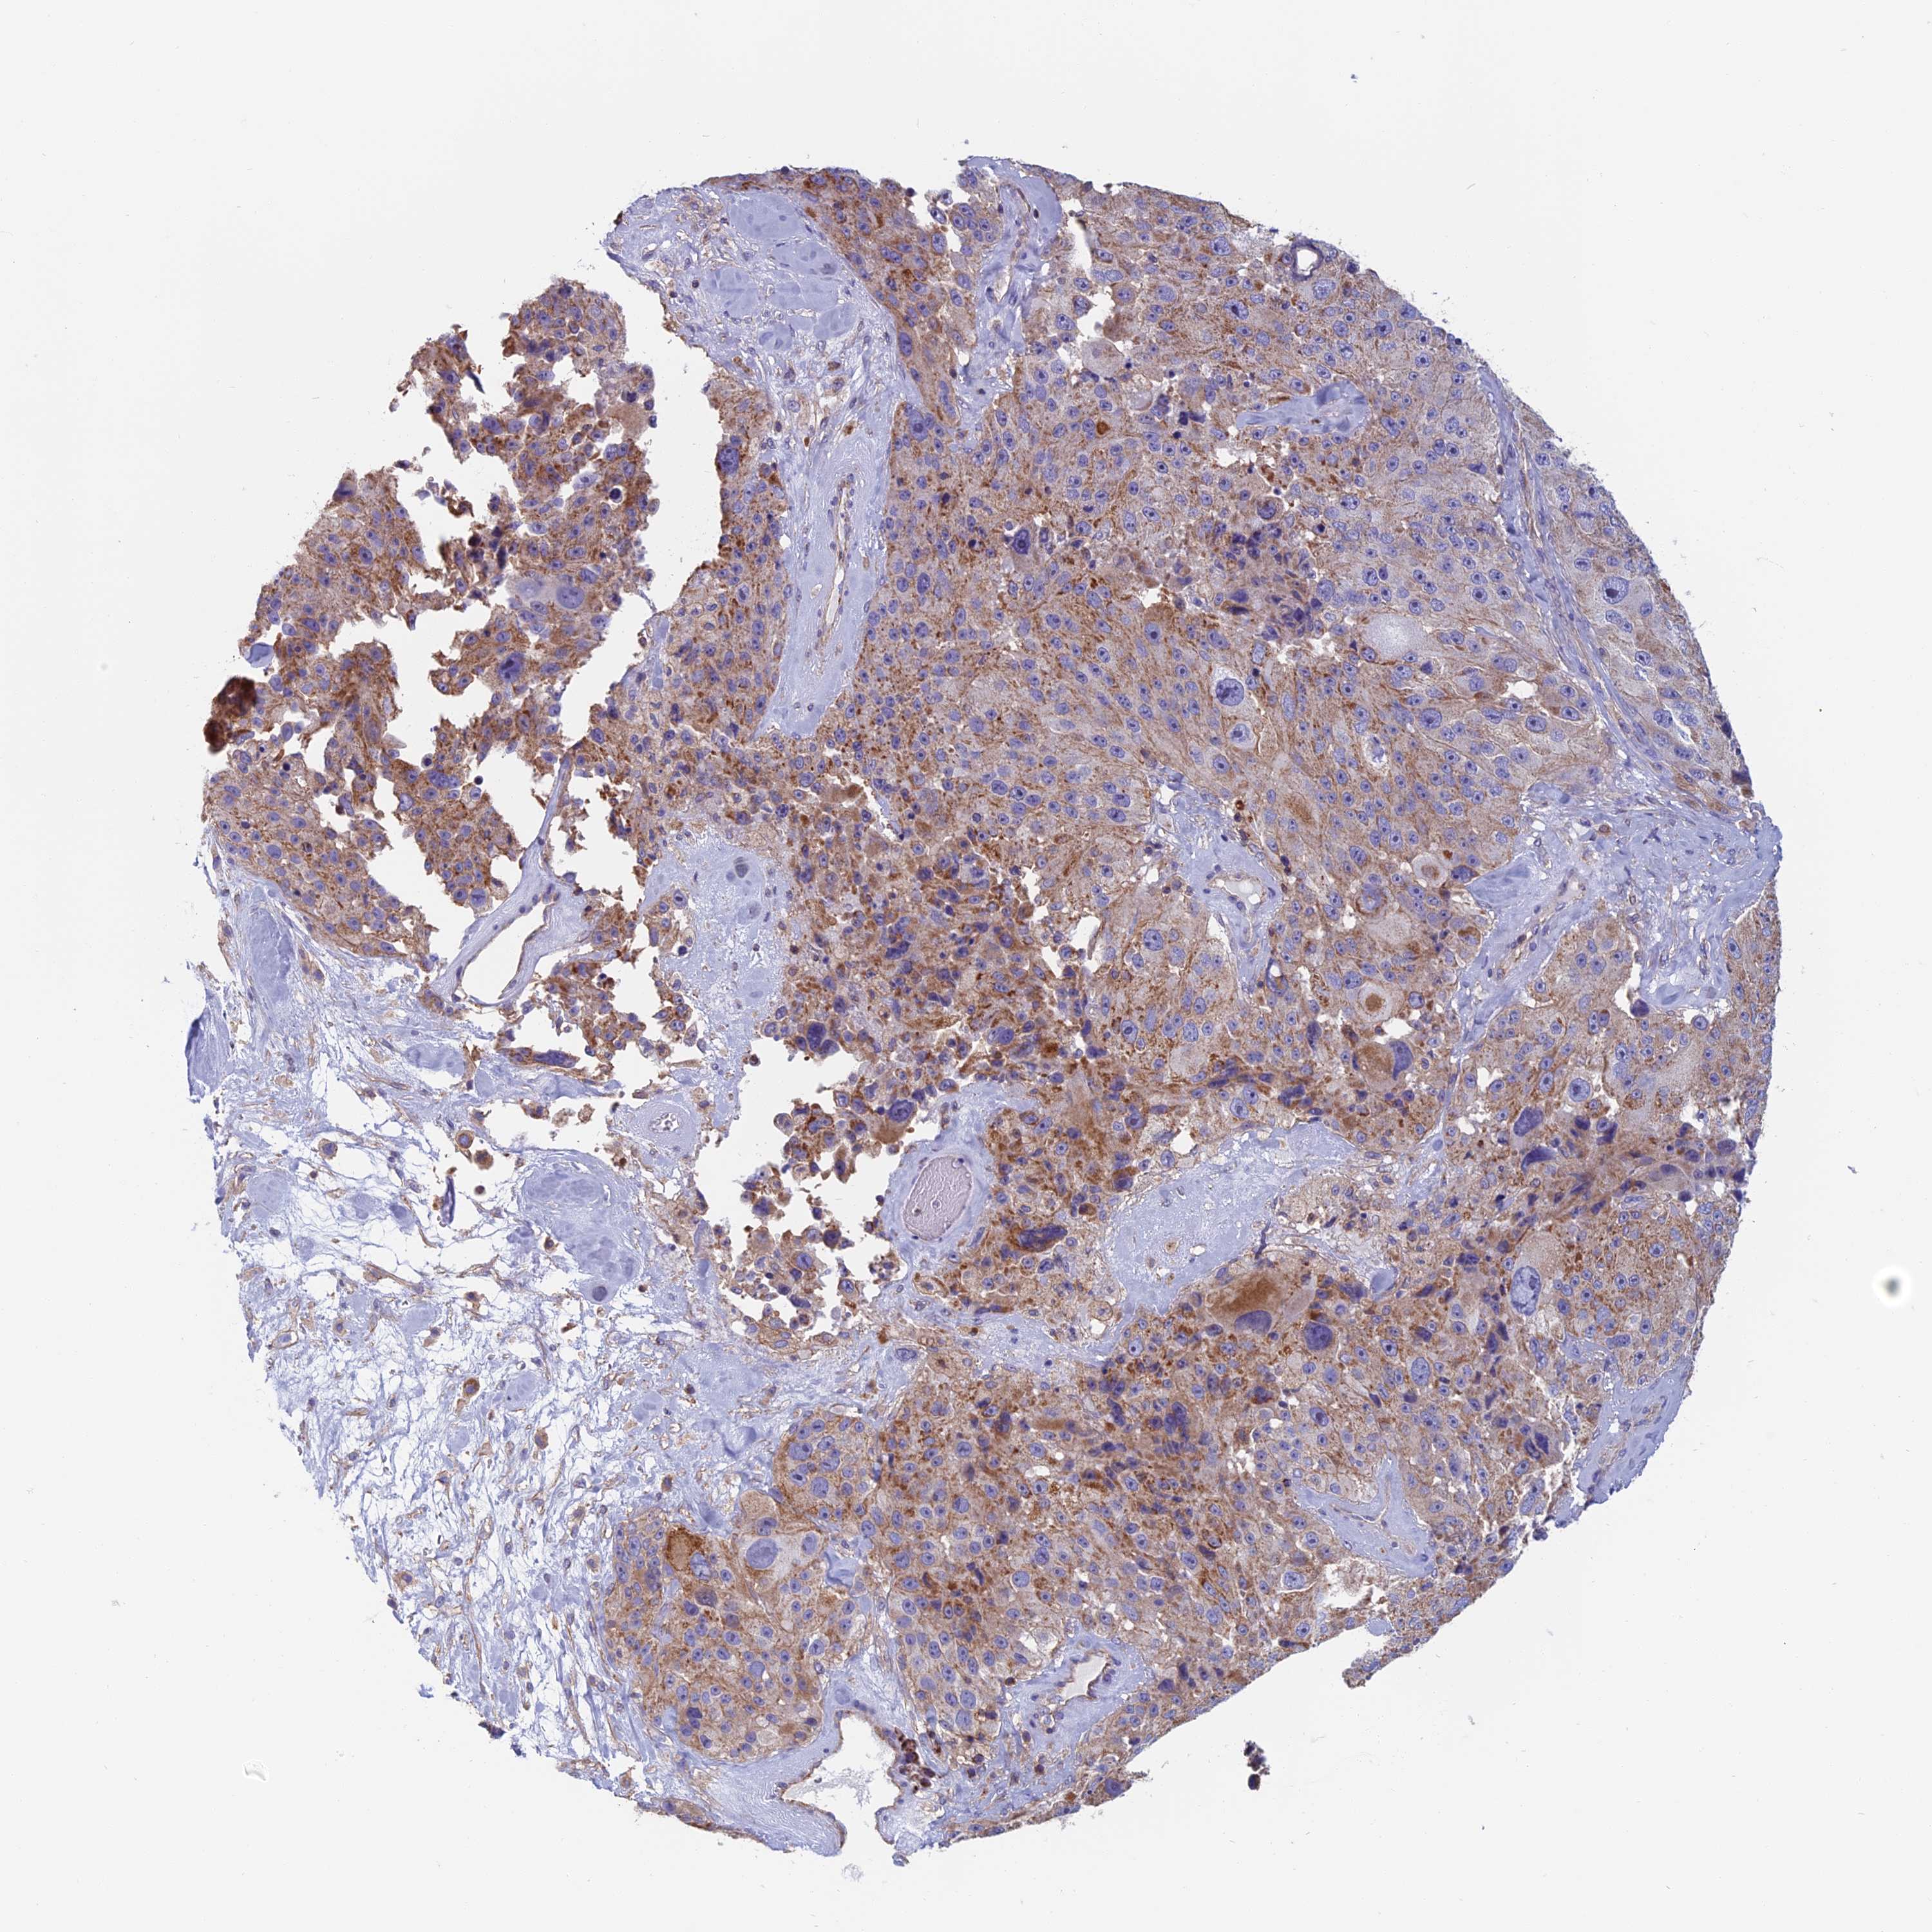

MELANOMA - Protein expressioni

A mouse-over function shows sample information and annotation data. Click on an image to view it in a full screen mode. Samples can be filtered based on level of antibody staining by selecting one or several of the following categories: high, medium, low and not detected. The assay and annotation is described here.

Note that samples used for immunohistochemistry by the Human Protein Atlas do not correspond to samples in the TCGA dataset.

Antibody stainingi

Antibody staining in the annotated cell types in the current human tissue is reported as not detected, low, medium, or high, based on conventional immunohistochemistry profiling in selected tissues. This score is based on the combination of the staining intensity and fraction of stained cells.

Each image is clickable and will lead to virtual microscopy that enables deeper exploration of all samples and also displays staining intensity scores, fraction scores and subcellular localization as well as patient and tissue information for each sample.

Antibody HPA042132

Staining

High

Medium

Low

Not detected

Intensity

Strong

Moderate

Weak

Negative

Quantity

>75%

75%-25%

<25%

None

Location

Nuclear

Cytoplasmic/membranous

Cytoplasmic/membranous,nuclear

Malignant melanoma, NOS